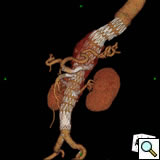

Planning

A clear understanding of the aortic, iliac and femoral anatomy based on preoperative imaging is critical to proper patient selection, device design, and accurate delivery. Other important anatomic details include a clear understanding of the relationships of all of the visceral and renal branch arteries to one another and their specific clockwise orientation to the aortic axis, the proximal seal zone, and aortic bifurcation (Figure 2). A site of delivery of the main body must be selected based on the size, extent of calcification and tortuosity of the access vessels. The procedures cannot be performed without accurate preoperative planning with the use of high resolution imaging and three-dimensional reconstruction techniques to be performed by the operator.